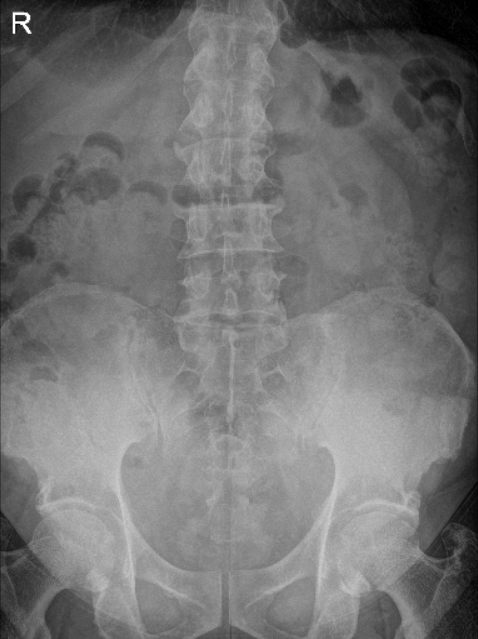

He presented X Ray of his bilateral knees, lumbar spine, and right hand from Zwanger. His Xray results showed mild osteoarthritic degenerative changes. There are no fractures. For his lumbar spine mild multilevel lumbar degenerative changes. For his right hand, normal right hand.

LS Spine X-ray Flex/Ext no obliques